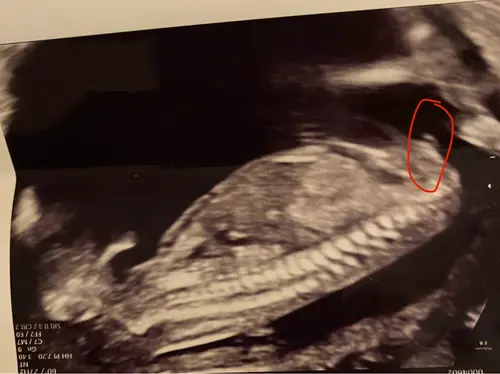

Hier geen nub te zien denk ik, toch? 13+5 🫣

En foto van het beentje, maar kan hier zelf ook niets uit halen 😆

Als het de nub is die ik denk te zien dan een meisje.

Meisje.🩷🩷